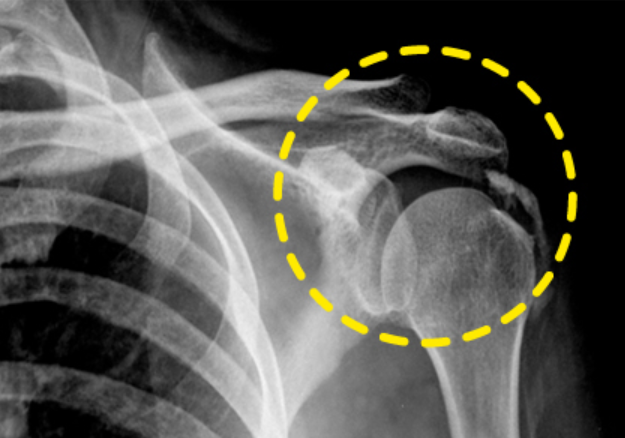

어깨통증 원인 네 번째는 석회성 건염입니다. 석회성 건염 역시 지속적인 통증보다는 갑작스럽게 어깨 부위에 심한 통증이 느껴질 때 의심할 수 있습니다. 이 때는 밤잠을 이룰 수 없을 정도로 고통을 주는데 보통 노화나 순환 장애로 어깨 부위 특히 힘줄에 칼슘이 축적되며 힘줄과 주변 조직에 통증을 유발하게 됩니다. 질병의 증상은 다양한데 해당 부위를 누르는 경우 심한 통증이 느껴진다면 우선적으로 석회성 건염일 가능성이 높으며 이때도 초음파 촬영이나 X레이 검사를 실시합니다.